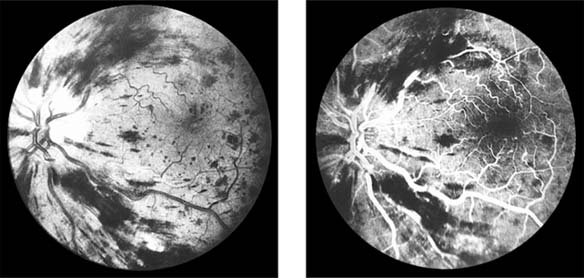

Figure 15-10: Accelerated hypertension. Fluorescein angiogram in a young man showing arteriolar constriction, dilation of capillaries with microaneurysms, and areas of closure. Marked disk edema is present.

In contrast, elderly patients with arteriosclerotic vessels are unable to respond in this manner, and their vessels are thus protected by the arteriosclerosis. It is for this reason that elderly patients seldom exhibit florid hypertensive retinopathy (Figure 15-11).

Figure 15-11

Figure 15-11: Accelerated hypertension. Fluorescein angiogram in an elderly wom.an showing marked arteriolar constriction and irregularity but few signs of florid retinopathy.

Fluorescein angiography has made possible accurate documentation of these microcirculatory changes. In young patients with hypertension, arteriolar attenuation and occlusion are seen, and capillary nonperfusion can be verified in relation to a cotton-wool spot, which is surrounded by abnormal dilated capillaries and microaneurysms with increased permeability on fluorescein angiography.

Resolution of the cotton-wool spots and the arteriolar changes occurs with successful hypotensive therapy. In elderly patients, the underlying arteriosclerotic changes are irreversible.